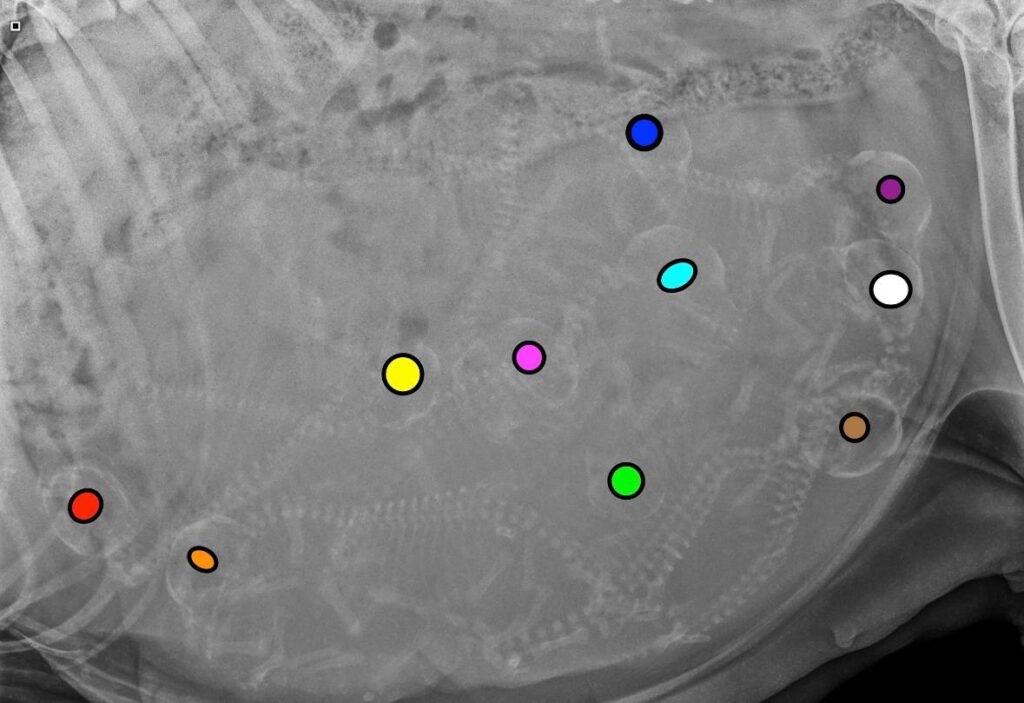

Vandaag heeft Fientje haar echo gehad.

Ik ben zo ontzettend blij, Fientje is drachtig!

Op de echo zijn meerdere pups te zien.

Ongeveer 8 maart 2026 is Fientje uitgerekend.